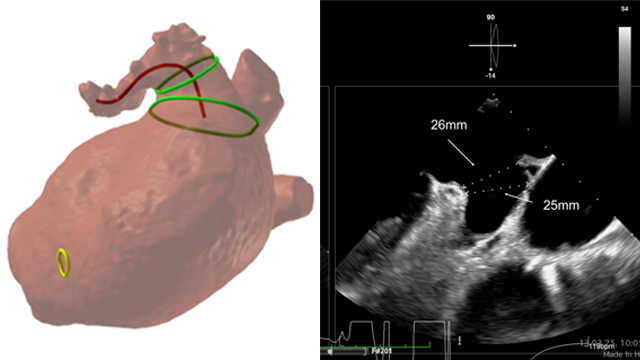

Severe MR in a high-risk patient with a suboptimal anatomy for M-TEER: what other options can we find?

Multimodality imaging reveals fibro-calcific leaflet disease, restricted motion, and a short posterior leaflet, making him a suboptimal candidate for M-TEER and prompting consideration of transcatheter mitral valve replacement. How would you treat?